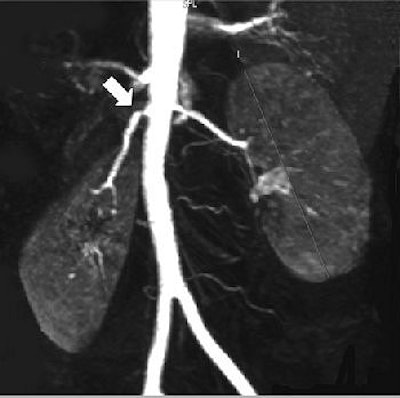

| Fifty-six-year-old healthy female living renal donor with stenosis of ostium of right renal artery. Above, volume maximum-intensity-projection MR angiography image using subtraction technique shows stenosis of ostium of right renal artery (arrow). Below, axial maximum-intensity-projection MR angiography image shows anterior origin of right renal artery with ostium stenosis (arrow). |